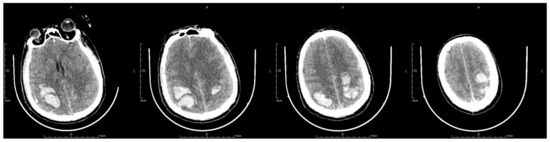

On the second postoperative day, the patient presented with idiopathic unconsciousness, limb twitching, and trismus. An emergency cranial CT scan demonstrated scattered hemorrhages in the bilateral frontoparietal lobes along with subarachnoid hemorrhages and edematous zones around some lesions (Figure 2 and Figure 3). Following an emergency consultation with the Department of Neurology and Neurosurgery, a diagnosis of venous sinus thrombosis combined with multi-focus cerebral hemorrhage was made. As per their orders, the patient underwent an emergency interventional intracranial angiography and thrombectomy.

Figure 2.

The letter R, A, P, L in the figures refers to Right, Anterior, Posterior and Left, respectively. Emergency CT scan showed scattered hemorrhages in bilateral frontoparietal lobes combined with subarachnoid hemorrhage and edema zones around some lesions (a–c).